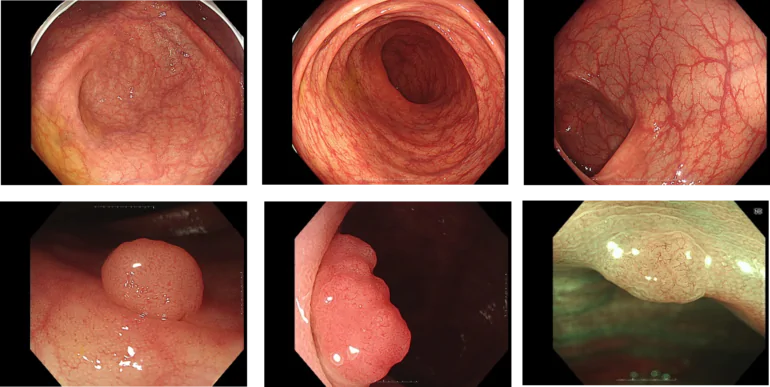

大腸カメラの症例

NBI(狭帯域光観察)

がんの増殖には血管からの栄養補給を必要とするため、病変の近くの粘膜には、小さな血管が集まりやすくなります。そのため、この小さな血管の集まりをいち早く発見することが、がんなどの病変の早期発見には重要です。

そのために用いられる技術が、「NBI(Narrow Band Imaging)」です。NBIは、血液中のヘモグロビンに吸収されやすい紫と緑の2つの特殊な光を照らすことで、粘膜表層の毛細血管やそのパターンなどが強調して鮮明に表示される観察技術です。これにより、通常光による観察では見えづらかったがんなどの病変の早期発見に貢献することが期待されます。

また、最適な治療判断には病変診断も重要となります。NBIは血管や粘膜の詳しい観察をサポートし、その診断にも貢献することが期待されます。

TXI(Texture and Color Enhancement Imaging)

色調の変化が小さい病変や凹凸の少ない平坦な病変は見つけにくいことがあります。この課題をクリアするために登場した「TXI(Texture and Color Enhancement Imaging)」は、画像処理技術によって病変をより見つけやすくすることを目指した画像強調技術です。

TXIは、粘膜表面の「構造」「色調」「明るさ」の 3 つの要素を最適化する画像強調技術です。通常光観察では見づらい画像上のわずかな色調や構造の変化が、TXI を活用することにより強調され、病変部などの観察性能向上に貢献することが期待されます。